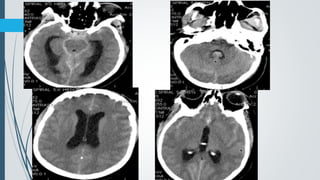

Acute SubacuteAcute

Chronic Acute on chronic

CT Findings

 Hyperacute

 Heterogenous or hypodense

 Acute

 60% homogenously hyperdense

 40% mixed hyper-, hypodense with active bleeding (Swirl sign)

 Subacute

 Iso to hypodense

 GM-WM junction displaced medially

 Progression from hyper to iso to hypodense over nearly 3 weeks.

 Recurrent hemorrhage results in mixed density.

 Chronic

 Typically follows CSF density

 Calcification can be seen along periphery of chronic collections, typically those

present for many years

** If no new hemorrhage, density decreases by +- 1.5 HU